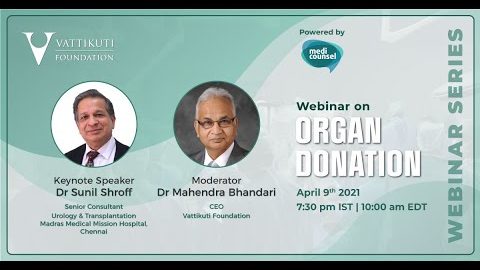

Organ Donation

Wellbeing ';